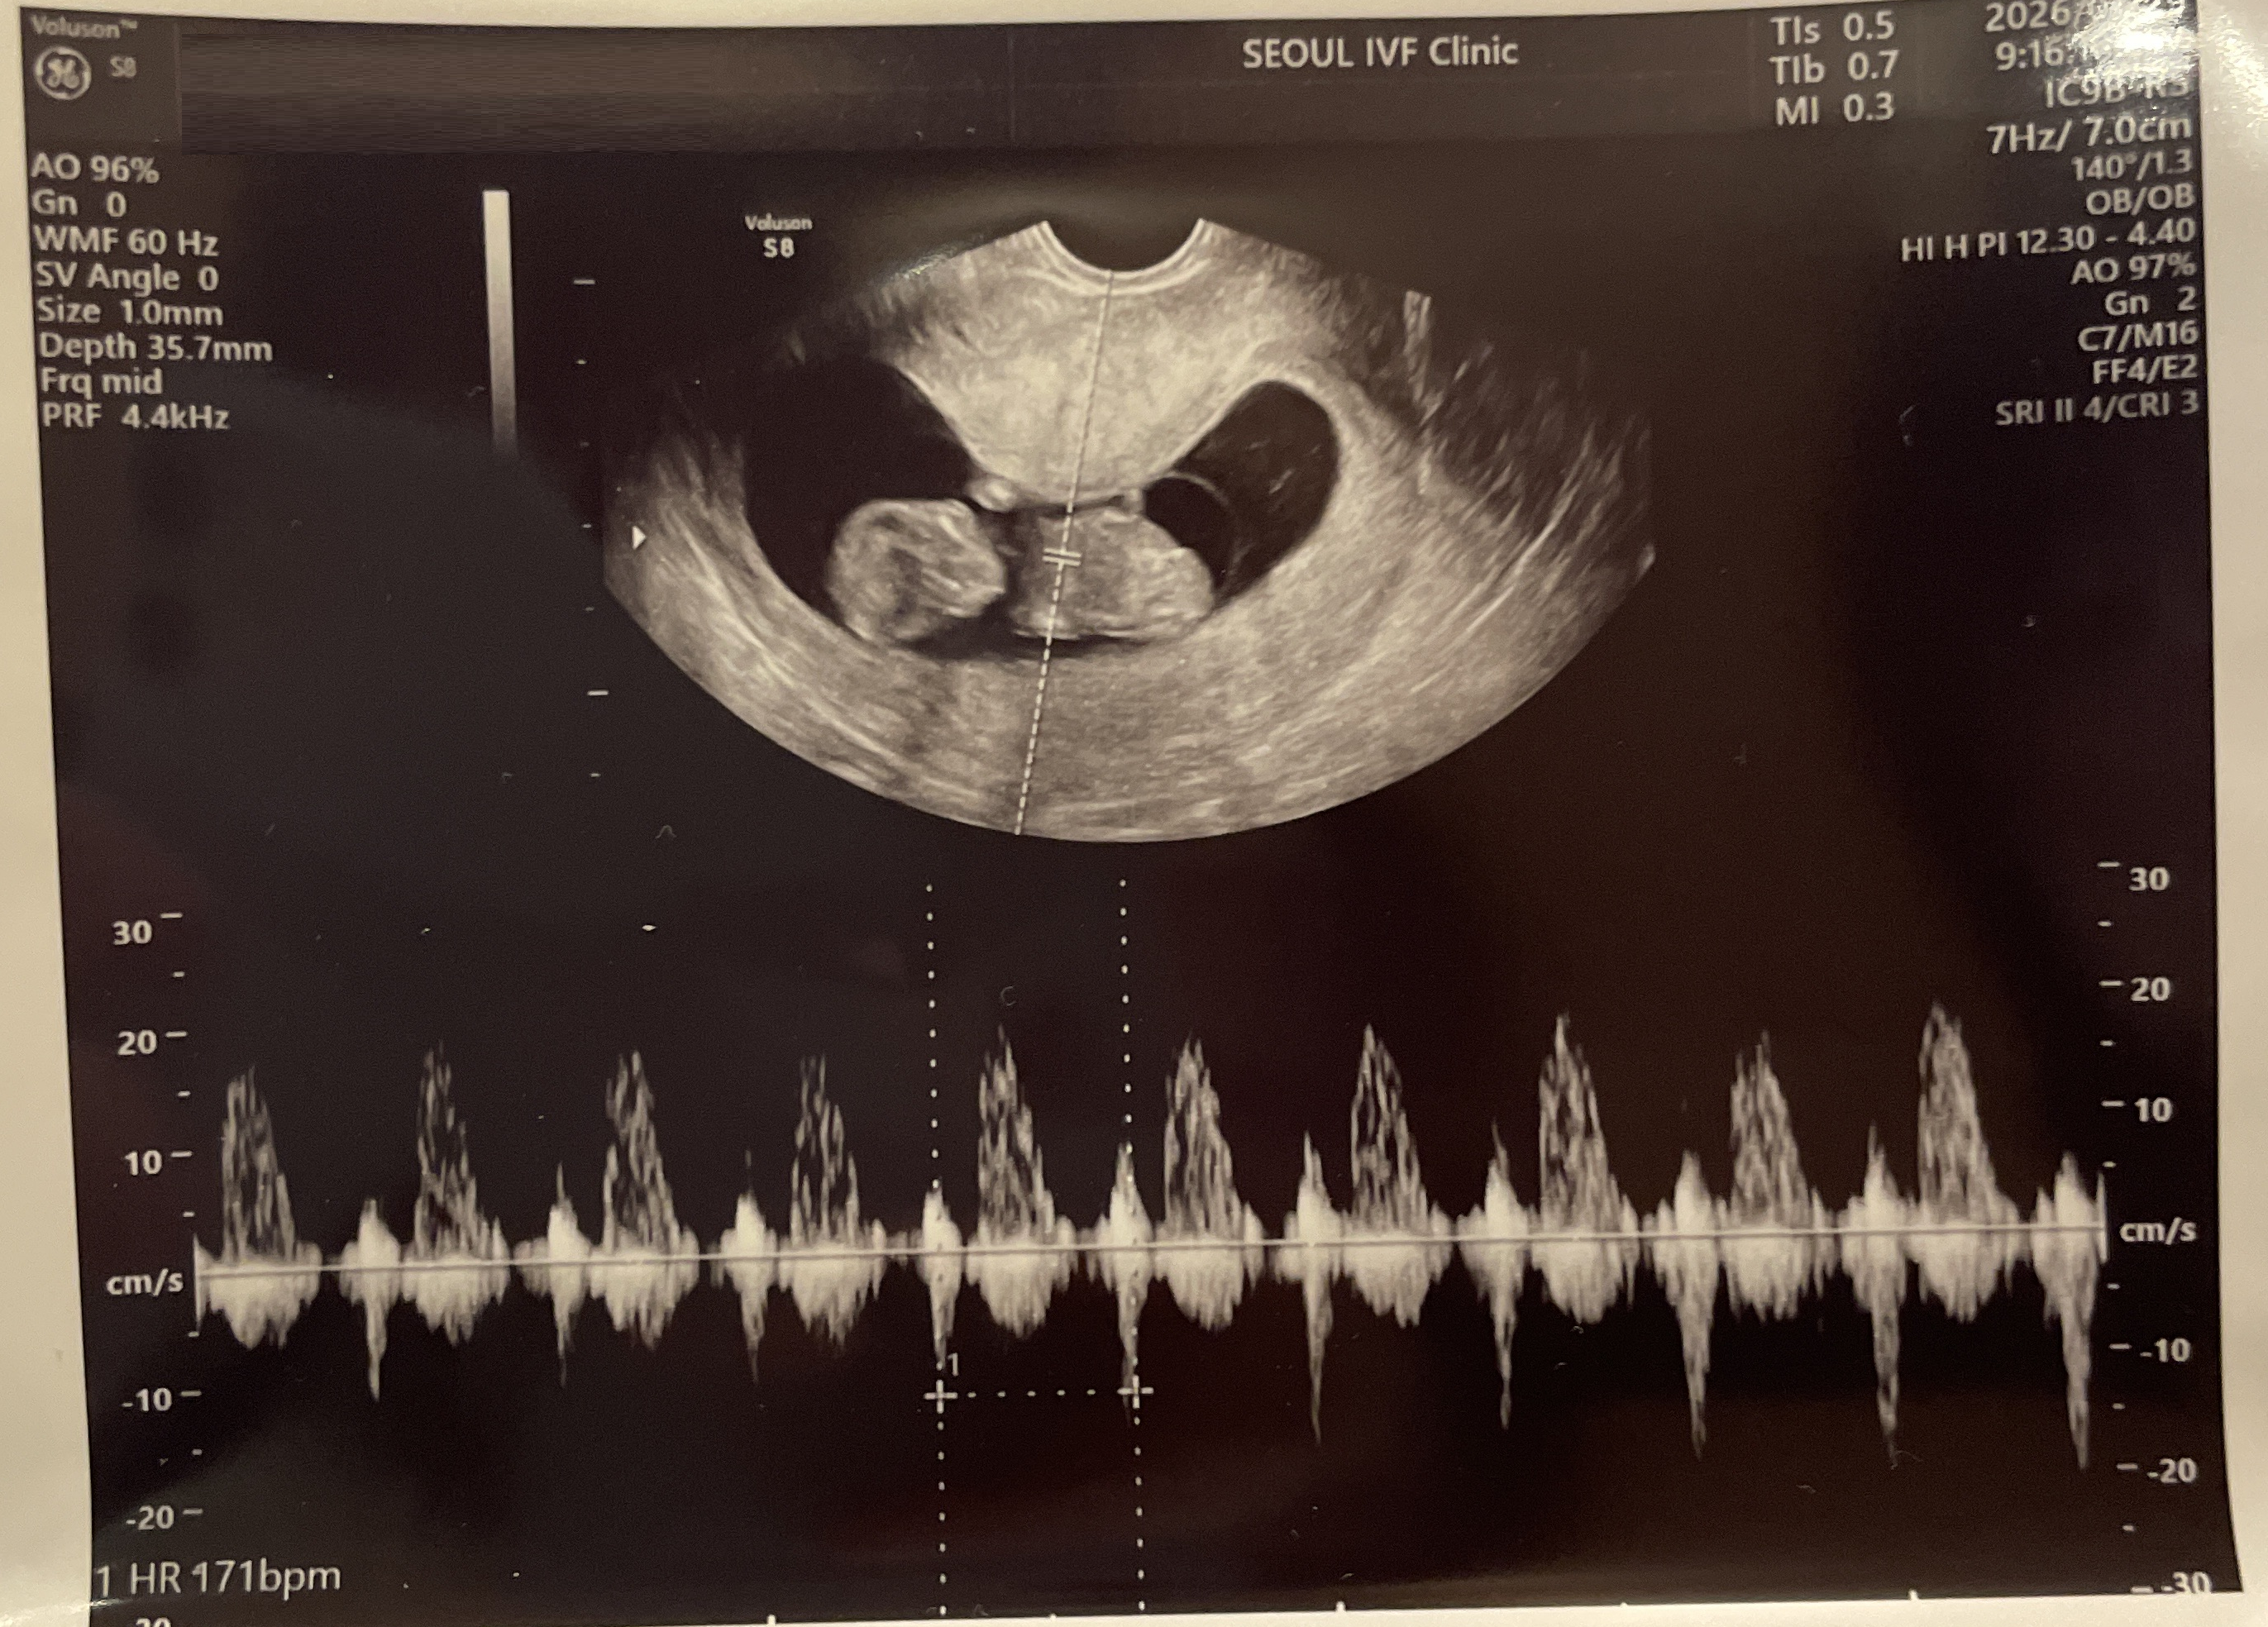

| 가슴 떨리는 임신 이야기를 공유해 주세요. | 기다림의 시간 끝에 시험관 2차 시도로 임신에 성공하게 되었습니다. 그 결과가 더욱 소중하게 느껴졌습니다. |

| 치료 도중 느꼈던 가장 기뻤던 순간과 절망적인 것들은 무엇인가요? 잊지 못할 경험이 있나요? | 가장 기뻤던 순간은 임신을 확인한 후 아기의 심장소리를 들었을 때였고, 가장 절망적이었던 순간은 1차 시도가 비임신으로 종결되었을 때였습니다. |